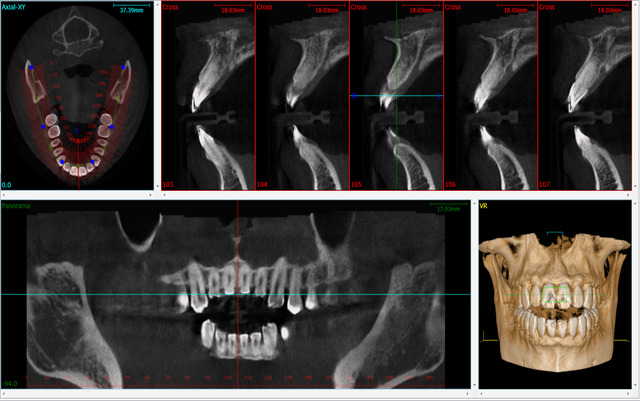

Our state-of-the-art scanning machine will take multiple scans and X-rays of your mouth and jaw, producing high-resolution 3D images of your mouth, including teeth, jaws, soft tissue, and bones – all with high levels of detail to enable precision planning to help fit your implant.

Jawbone density can naturally decrease when teeth are missing. If our high-resolution 3D CBCT scans reveal that you require additional bone support, you will not need an outside referral.

During this detailed appointment at our Mutley Plain clinic, we assess your gum health, the structural integrity of your teeth, and bite function. We utilise a state-of-the-art scanning machine to take high-resolution 3D images and X-rays of your mouth.